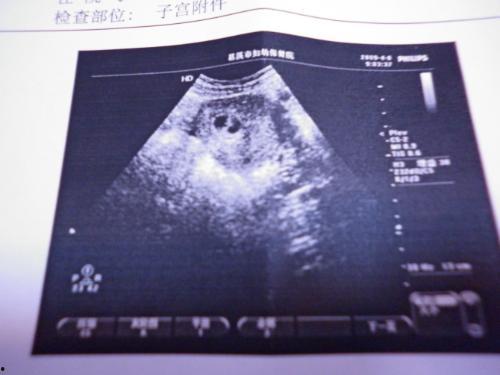

接下来,咱们聊聊B超。B超,全称超声波检查,是一种无创、无辐射的检查方法。它通过发射超声波,探测人体内部器官的形态、大小和位置,从而帮助医生诊断疾病。

那么,吃二甲双瓜可以做B超吗?答案是可以的。B超检查并不受食物的影响,只要不是特别油腻或者含有金属等特殊成分的食物,都不会影响B超的检查结果。